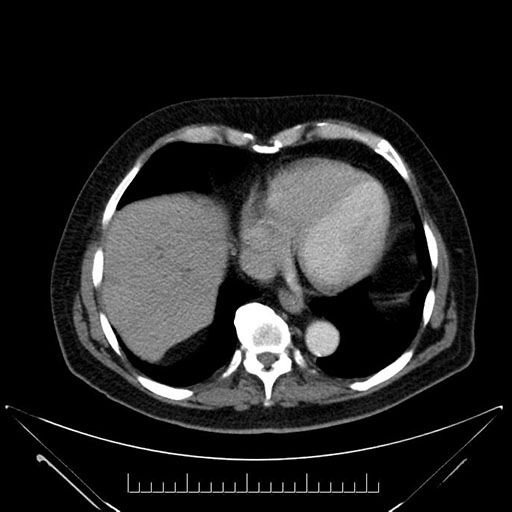

Whipple (pancreaticoduodenectomy) [case 7]

Imaging Analysis

Look through the patient's CT scan to identify any areas of concern for the necessary procedure.

Axial - 3 months prior